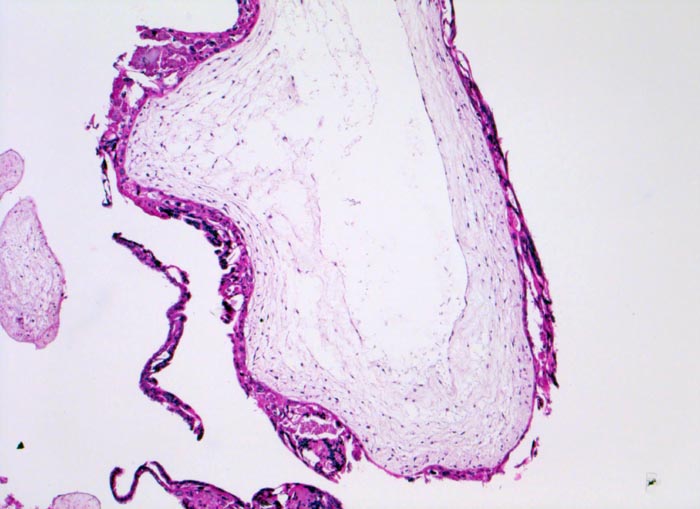

Makroskopisch ist die Plazenta deutlich grösser als erwartet für das Schwangerschaftsalter. Sie ist diffus von bis 2cm grossen Zottenblasen durchsetzt, welche nach Kollaps jedoch der makroskopischen Entdeckung entgehen können. Beim Aufschwemmen in Flüssigkeit entfalten sich die Blasen wieder. Mikroskopisch sind die Zotten aufgrund einer grobblasigen pseudozystischen Hohlraumbildung im Zottenstroma überwiegend grosskalibrig. Im Zottenstroma sind nur ganz vereinzelt Kapillaren nachweisbar. Im Gegensatz zu hydropisch geschwollenen Zotten im Sinne eines Regressionsphänomens zeigen die Zotten bei Blasenmole zusätzlich eine zirkumferentielle Hyperplasie von Synzytio- und Zytotrophoblast mit fakultativer Zellatypie. Bei herdförmiger Mole (> 3725) sind diese Veränderungen nur in einem Teil der Plazentarzotten ausgeprägt.

• Stark vergrösserte und verplumpte Plazentarzotten.

• Hydropisch umgewandeltes Zottenstroma ohne Gefässe mit Ausbildung von pseudozystischen Hohlräumen (Blasen)

• Deziduafragmente